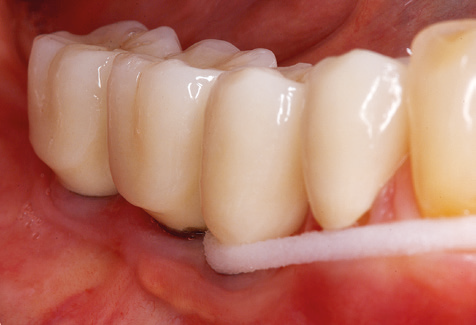

Nach der maschinellen Reinigung der Zahn und Implantatoberflächen erfolgt eine manuelle Instrumentierung der natürlichen Zahnoberflächen mit konventionellen Handinstrumenten. Bei der manuellen Reinigung ist insbesondere auf einen korrekten Anstellwinkel, eine ausreichende Schärfe, eine gute Abstützung und auf eine von apikal nach koronal gerichtete Arbeitsweise der Kürette zu achten. Zur Nachinstrumentierung der Implantatkonstruktionen sollten entweder Titan oder Carbonküretten verwendet werden (Abb. 8). Ergänzend zum Einsatz von Ultraschallgeräten können in der Erhaltungstherapie auch Pulverstrahlgeräte genutzt werden. Dabei ist jedoch zu berücksichtigen, dass diese Verfahren nicht zum Entfernen harter Beläge geeignet sind und daher die Verwendung von Hand oder Ultraschallinstrumenten nicht komplett ersetzen können. Abschließend erfolgt in jedem Fall eine mechanische Politur der zugänglichen Zahn und Implantatoberflächen mit Polierkelchen und Polierpasten (Abb. 9).